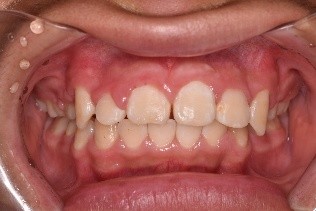

(初診時) (ワイヤー除去前) (ワイヤー除去後)

※この方はワイヤー矯正後、マウスピース矯正に移行しています

(↑マウスピース矯正後)

1~2か月毎にワイヤー矯正と同様に経過観察に来ていただきます。上の写真がマウスピース矯正後の口腔内です。きれいな歯並びになりました!